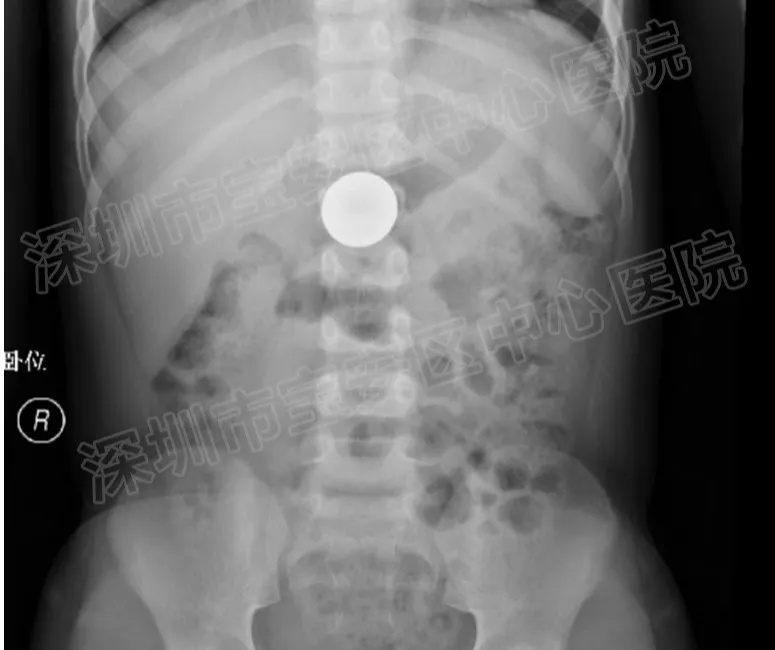

医生开具腹部立位片后发现,硬币还在小豪胃里。